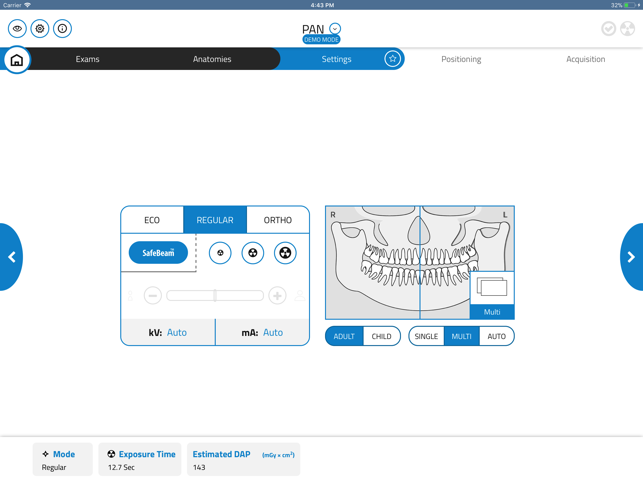

GiANO HR is a highly advanced dental equipment by NewTom, with panoramic, ceph and CBCT capabilities. NewTom Control Pad allows GiANO HR users to connect via Wi-Fi to the equipment, browse the diagnostic programs available, select an imaging modality and a region of interest before performing a radiographic examination.

NewTom Control Pad does not replace any PC workstation, where NewTom NNT imaging software will process and store the radiographic data. Nevertheless, NewTom Control Pad provides quick and easy previewing of 2D radiographs acquired, with image enhancement such as brightness, contrast and gamma correction, as well as e-mailing of 2D images to a preferred recipient.